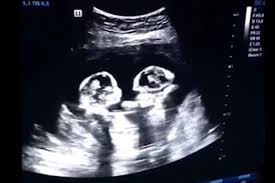

متى يظهر كيس الحمل بتوأم بالسونار أنا مامي